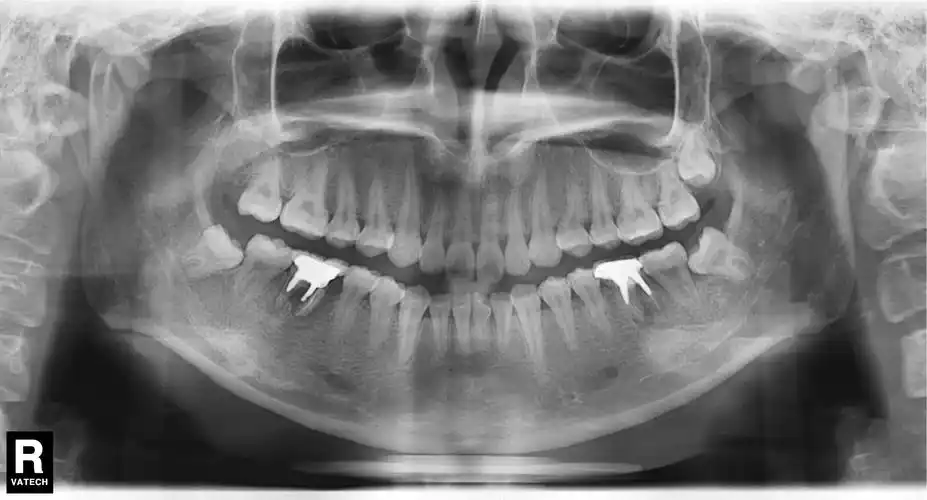

低位埋伏阻生智齿 牙源性囊肿处理 - 知乎

我的牙齿片子已经拍了,医生说有一个大的囊肿,请教,怎么办? - 知乎

请问这张片下面牙齿下方的阴影是囊肿吗?严重吗?是不是一定要做手术?

含牙囊肿影像诊断